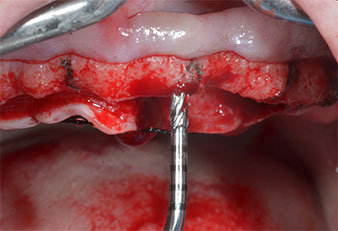

Ein flammenförmiges, diamantiertes piezochirurgisches Instrument (Piezomed I1) wurde verwendet, um die Implantatpositionen zu markieren und die Pilotpräparationen durchzuführen (Abb. 3). Dabei wurde darauf geachtet, eine Auf- und Abbewegung mit reduzierter Leistung, voller Spülung und niedrigem Druck (unter 300 g) anzuwenden. Als Nächstes wurde ein Pilotinstrument (Piezomed I2A/I2P) zur initialen Erweiterung der Implantatlager auf einen Durchmesser von 2 mm verwendet (Abb. 4), gefolgt von einem 3-mm-Instrument (Abb. 5).

Abb. 5: Der abschließende Durchmesser wird mit den Instrumenten Piezomed I3A/I3P erreicht. Die Implantatlager für die 10-mm-Implantate an Position 11 und 21 werden mit einem Implantatmotor (Implantmed) mit einem 3,5-mm-Spiralbohrer fertiggestellt.

Abb. 4: Der nächste Schritt ist die initiale Erweiterung mit den Instrumenten Piezomed I2A/I2P, die in einer horizontalen Drehbewegung verwendet werden.